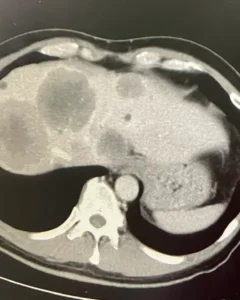

CT画像で肝臓全体にがんが広がっていることを自分の目でも確認。

がんの大きさは13センチ以上。それがいくつもある・・・。もう手術も放射線治療もできないらしい。完全に手遅れ状態でしょうか・・・そのまま入院となり、唯一できること、「抗がん剤治療」の準備を進めることにしました。